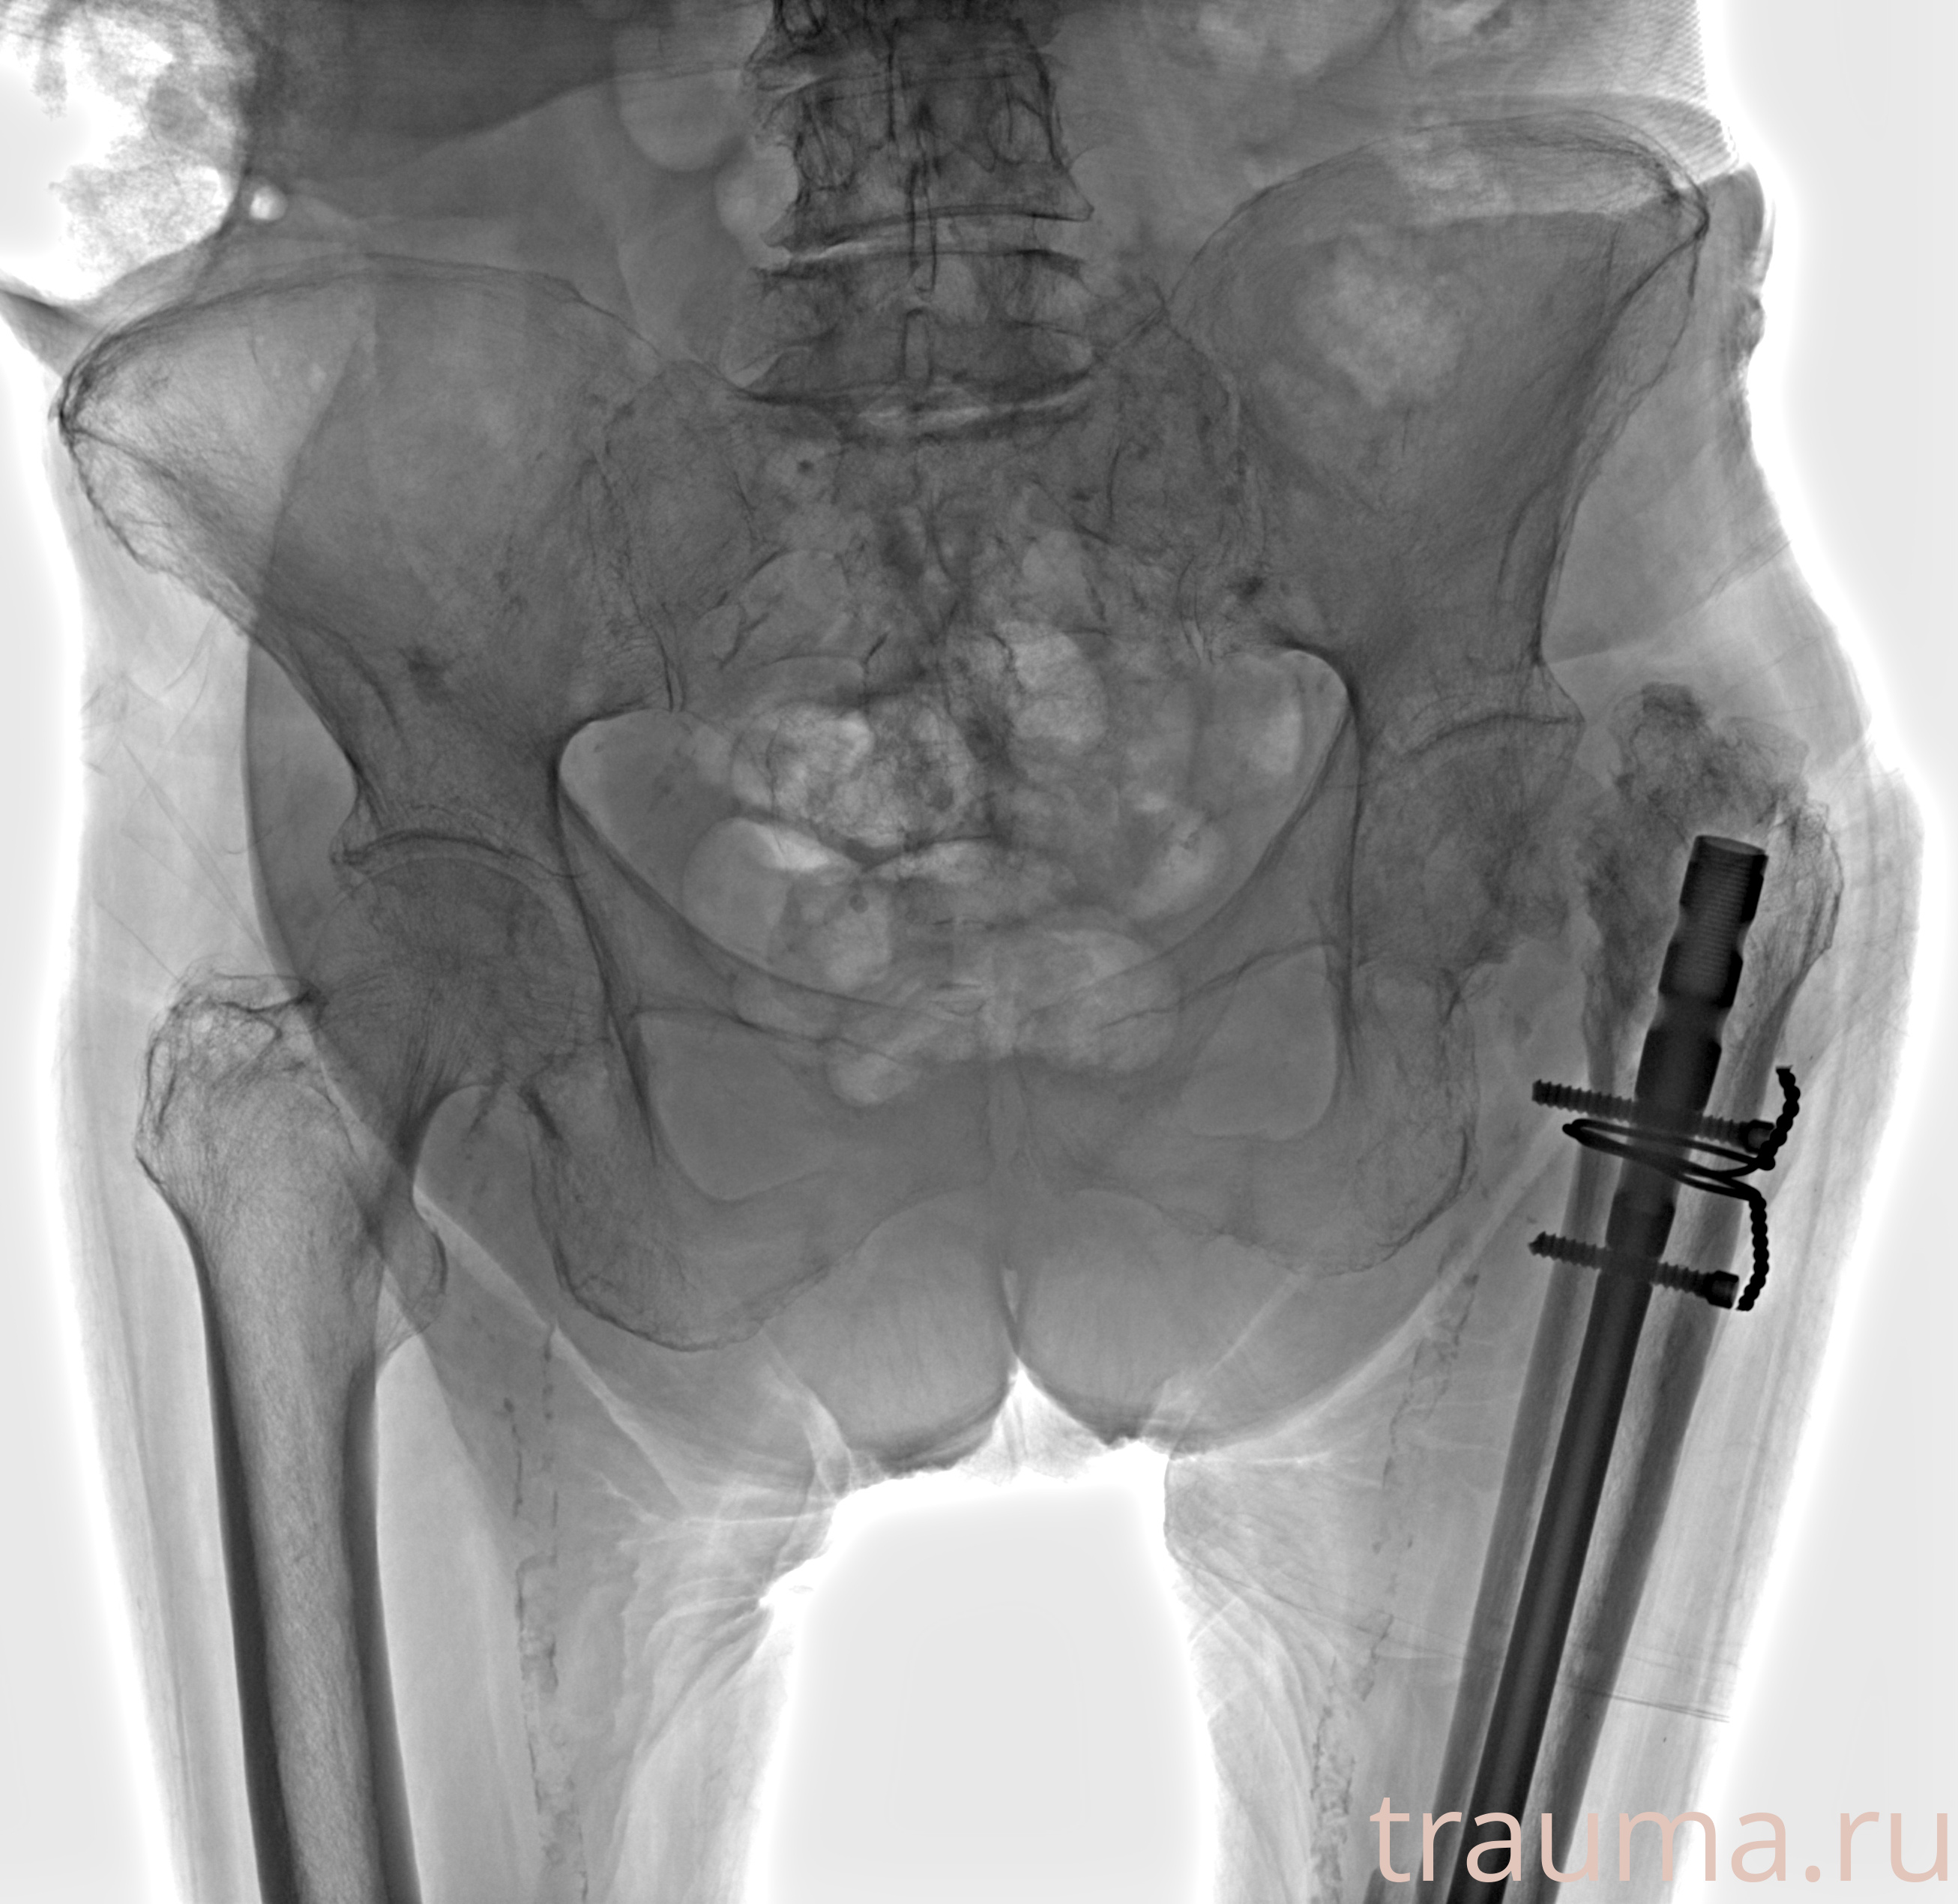

Рентгенограммы

Рентген на дому: по вашему адресу приезжает врач-рентгенолог, травматолог-ортопед с мобильным рентгеновским аппаратом, проводит диагностику травмы или заболевания, делает необходимые рентгенограммы, дает рекомендации по дальнейшему лечению. Получить качественные снимки в домашних условиях возможно благодаря уникальной методике, разработанной МосРентген Центром для института  Склифосовского

при переломе шейки бедра и пневмонии от компании МосРентген Центр - партнера Института имени Склифосовского